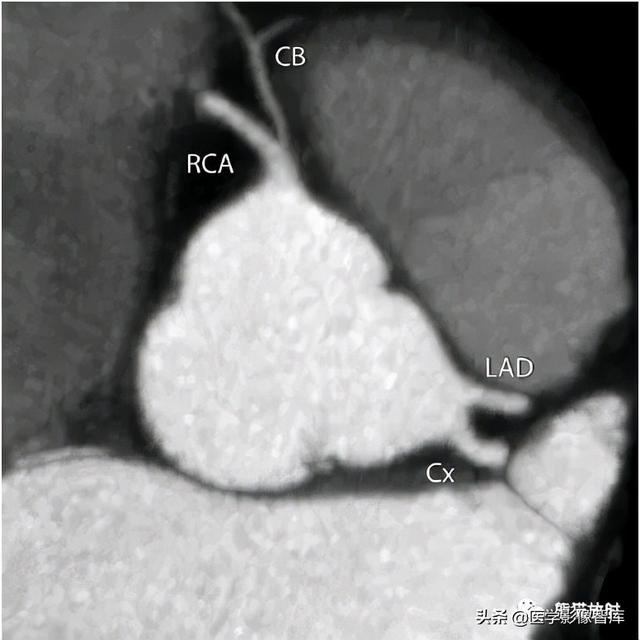

图4 左主干缺如

平行于主动脉根部的双斜位显示左前降支(LAD) 和回旋支(Cx) 分别开口于左冠窦。左主干缺如,右冠状动脉(RCA) 发出圆锥支(CB)